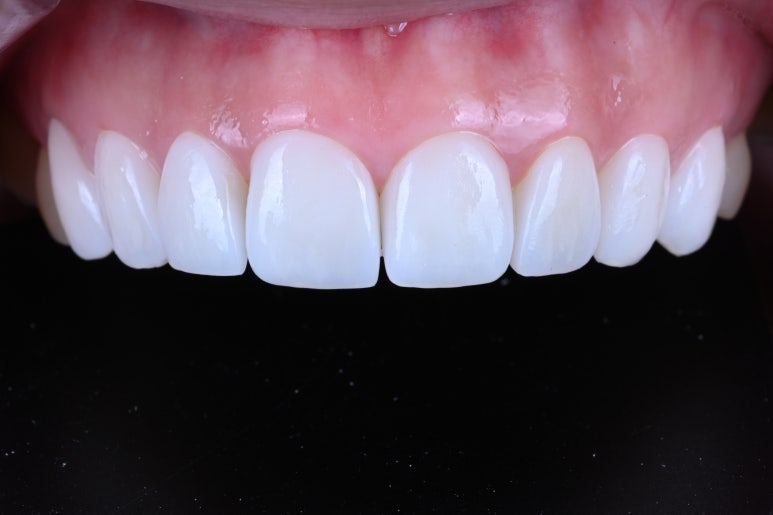

그리하여 완성된 레브네이트 엑스퍼트..

화사한 색감이 생겼습니다.

그리고 도자기처럼 반딱거리는 인공적인 느낌이 아니라, 표면에 세라믹 가공을 첨가하여 약간의 텍스처를 부여한 덕에 자연스러움까지 추가되었습니다.

뭔가 밝아지긴 했는데... 하얘진건 맞는데 자연스럽다는 것..

이게 뭐라 설명하기 어려운 작품의 세계라고 해야할 것 같아요.

앞니만 봤을 때도, 확실히 다른 느낌인 것을 확인하실 수 있어요.